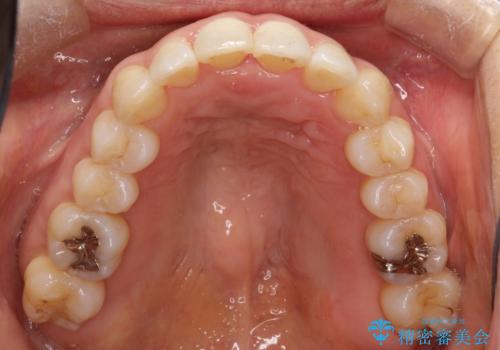

重度のガタガタのインビザラインによる非抜歯矯正

しっかりとマウスピースを使用していただけたので、順調に治療を終えることができました。